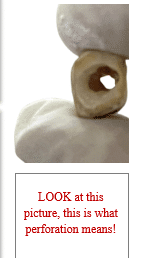

Coronal perforation means accidental mechanical communication between the pulp chamber and external PDL or outer of the tooth during access cavity preparation.

The crown has been perforated ( a hole in the tooth).

Common locations: furcation, buccal/lingual walls.